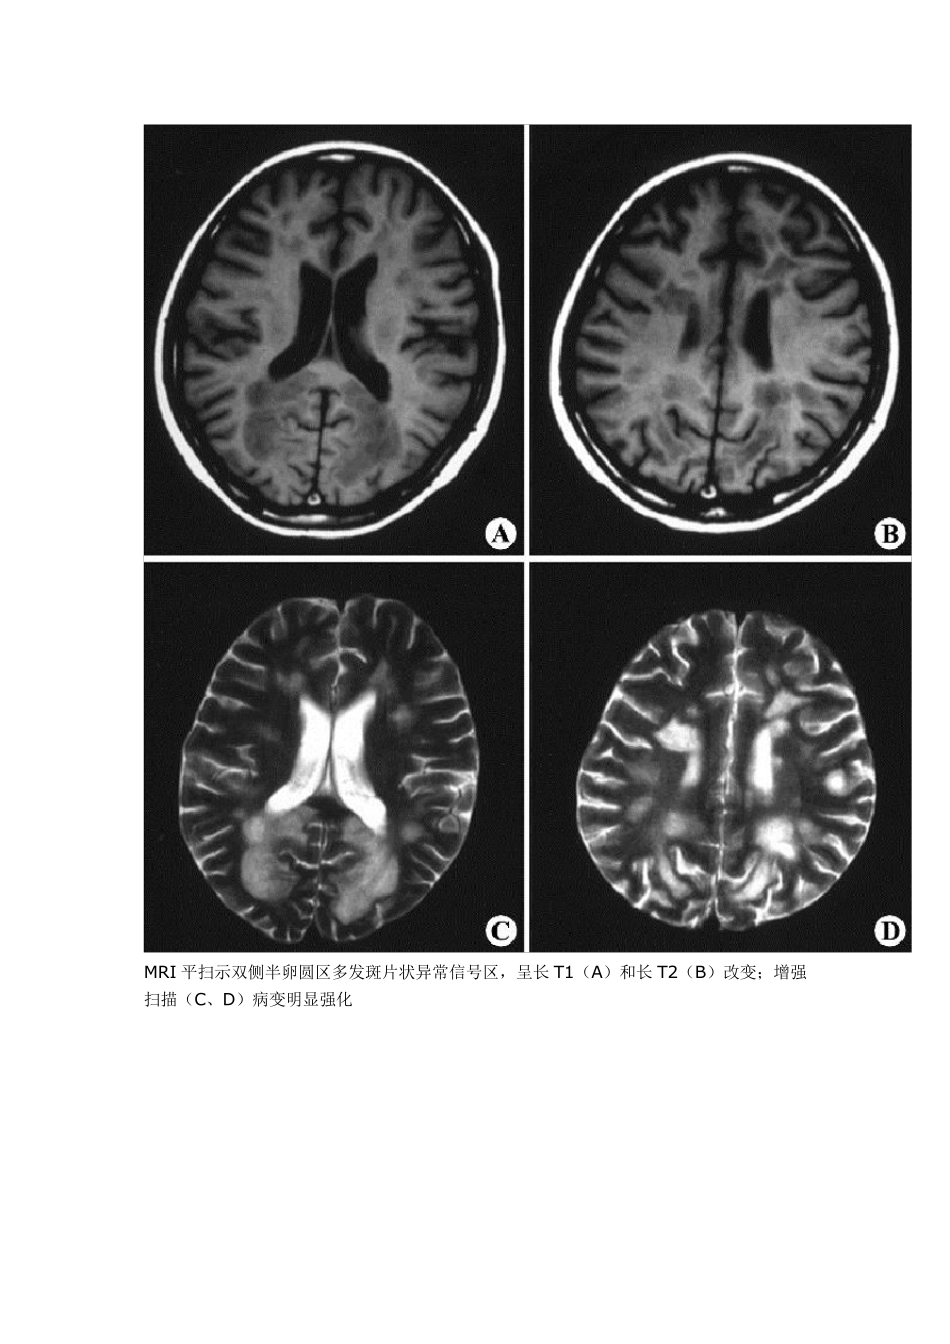

多灶性脱髓鞘: 1.多发硬化(Mu ltiple Sclerosis ,MS):中枢神经系统脱髓鞘疾病中最常见的一种类型,患者脑和脊髓内发生多灶性脱髓鞘斑块为其主要表现。 1.1 病理:病灶主要位于脑和脊髓的白质内,呈弥散分布。大脑半球大体观可正常,部分人有脑回轻度萎缩及脑沟增宽;切面可见大小不等的软化坏死灶和边缘清楚的灰色斑块,以侧脑室周围和小脑多见。显微镜检查:早期 病灶区髓鞘崩解,局部水肿,血管周围有淋巴细胞、浆细胞浸润等炎症反应。中期随髓鞘崩解产物被吞噬细胞逐渐清除,形成斑点状软化坏死灶,可见格子细胞形成 和轴索消失。晚期病灶区有胶质细胞与星形细胞增生,网状与胶原纤维增生,形成边界清楚的灰色斑块,直径一般在 0.1cm ~4.5cm 。病灶可新旧并存。重 症、晚期患者可见脑室扩大,脑回变平,脑沟增宽和脊髓变细等脑脊髓萎缩改变。偶尔MS 可伴胶质瘤,肿瘤起源于多发硬化的斑块。 1.2 影像学:MRIT1 加权像见多发斑点状低信号病灶,通常与侧脑室壁垂直排列,与脑室周围白质内小血管的走行方向一致。陈旧性斑块呈等信号。由于多发硬化是少突神经胶质-血管髓磷脂复合疾病,因此有5%者,皮质和基底节亦受累,半卵圆中心的病灶可有占位效应。脊髓病灶呈长 条形,与脊髓长轴走行一致,一般脊髓不增粗。T2 加权像病灶呈高信号,边缘清晰。质子密度加权像有利于显示靠近脑室边缘、脑干及小脑MS 病灶。Gd- DTPA增强扫描 T1 加权像急性脱髓鞘病灶强化,陈旧病灶无强化。 MRI 可判断 MS 的分期:MRI显示病灶大小不变、病灶缩小或数目减少,则提示为缓解期;若病灶增大或数目增多,则提示病情加重。MRI 还可用来随访治疗效果。 MRI 平扫示双侧侧脑室周围及深部脑白质多发斑片状异常信号区,T1WI(A、B)呈低信号,T2WI(C、D)呈高信号,未见占位效应 MRI 平扫示双侧半卵圆区多发斑片状异常信号区,呈长T1(A)和长T2(B)改变;增强扫描(C、D)病变明显强化 双侧幕上半球放射冠区多发斑片状异常信号区。T1W I(A)为稍低信号,T2W I(B)为高信号,FLAIR(C)呈不均匀稍高信号,占位效应不明显。 肿块样的ms,但较之肿瘤水肿轻,和对白质压迫的作用。 1.3MS 影像学鉴别诊断: 1.3.1 皮层下动脉硬化性脑病(Binsw anger 病):Binsw anger 病与高血压有关,对长期高血压和进行性痴呆的患者,结合脑MRI 表现可诊断此病.为老年人在脑动脉硬化基础上,大脑半球白质弥漫性脱髓鞘性脑病。主要累及侧脑...